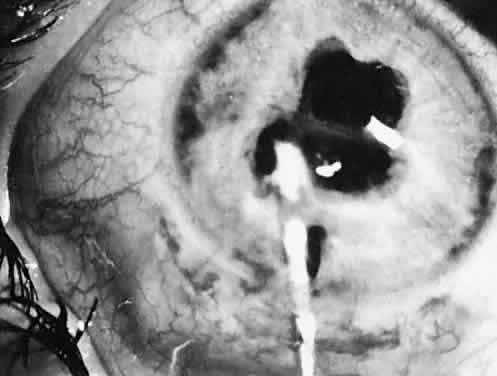

Eyes with pediatric cataracts appear to have an abnormal outflow facility and a propensity for open-angle glaucoma. Simon and colleagues52 reported glaucoma in 24% of eyes treated for cataracts and followed for at least 5 years. Johnson and Keech53 reported glaucoma in 32% of patients with PHPV-type cataracts (eight of 25) and the same 32% in patients with infantile cataract (15 of 47). The mean time of onset of glaucoma was 65 months and 47 months after surgery, respectively. Chrousos and associates38 found chronic glaucoma in 6.1% of treated eyes. Eyes with rubella, uveitis, or microphthalmia are particularly affected. A slightly more anteriorly placed incision and careful wound closure prevent iris-to-cornea adhesions. Figure 31 shows a gonioscopic view of an angle of a 5-year-old child in whom late-onset glaucoma developed after cataract surgery. Walton51 has described a near-constant (96%) but variable angle defect characterized by blockage of the trabecular meshwork by an acquired repositioning of the iris against the posterior trabecular meshwork.